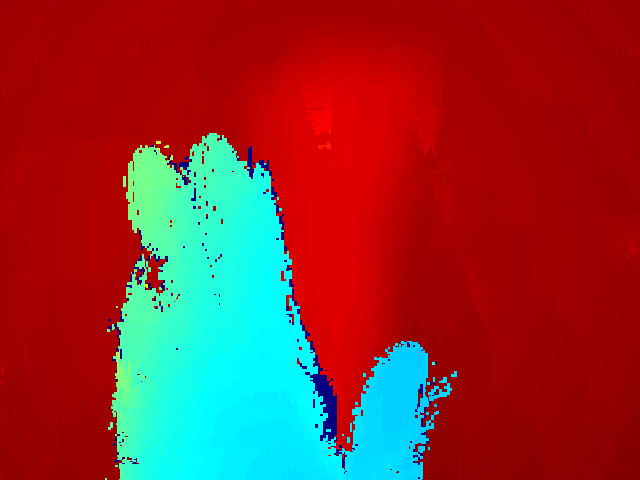

As a first step, the foreground needs to be segmented from the synthesized video image Icsubscript𝐼𝑐I_{c} and depth image Idsubscript𝐼𝑑I_{d}. A background model is computed from an initialization sequence of depth images where no hands or surgical instruments are introduced yet. An average depth image is created by averaging the depth at every pixel along the initialization sequence. Then, for every new image (with potential hands or surgical instruments present), the depth image Idsubscript𝐼𝑑I_{d} is compared to the mean image in order to create a binary mask image Imsubscript𝐼𝑚I_{m}. For every pixel whose depth is lower than the average depth minus a margin (3 cm), the pixel is classified as foreground and is set as white in Imsubscript𝐼𝑚I_{m}. If the pixel is classified as background, then it is set as black in Imsubscript𝐼𝑚I_{m}. The method is rudimentary compared to background subtraction methods, however the margin allows the background to change shape (in the limit of the margin). A noise removal step is added using morphological opening on the mask image. An example of scaled depth image and its corresponding mask are shown on Figure 3.

Refer to caption

Figure 3: The synthesized depth image and its corresponding segmented mask